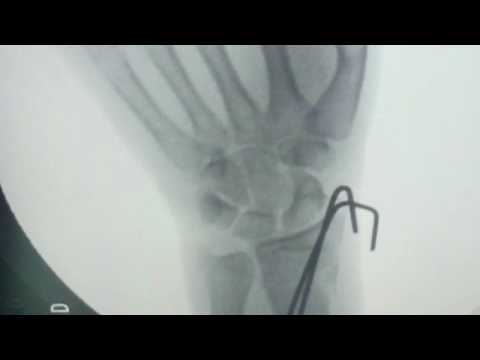

La traumatología es la especialidad médica que se enfoca en el diagnóstico y tratamiento de lesiones y condiciones que afectan el sistema musculoesquelético. Gracias a los canales de traumatología en plataformas digitales, pacientes y profesionales pueden acceder a información valiosa sobre lesiones, rehabilitación y prevención de problemas ortopédicos. Estos canales son recursos esenciales para aquellos que buscan mejorar su salud física y conocer más sobre el cuidado de su cuerpo.